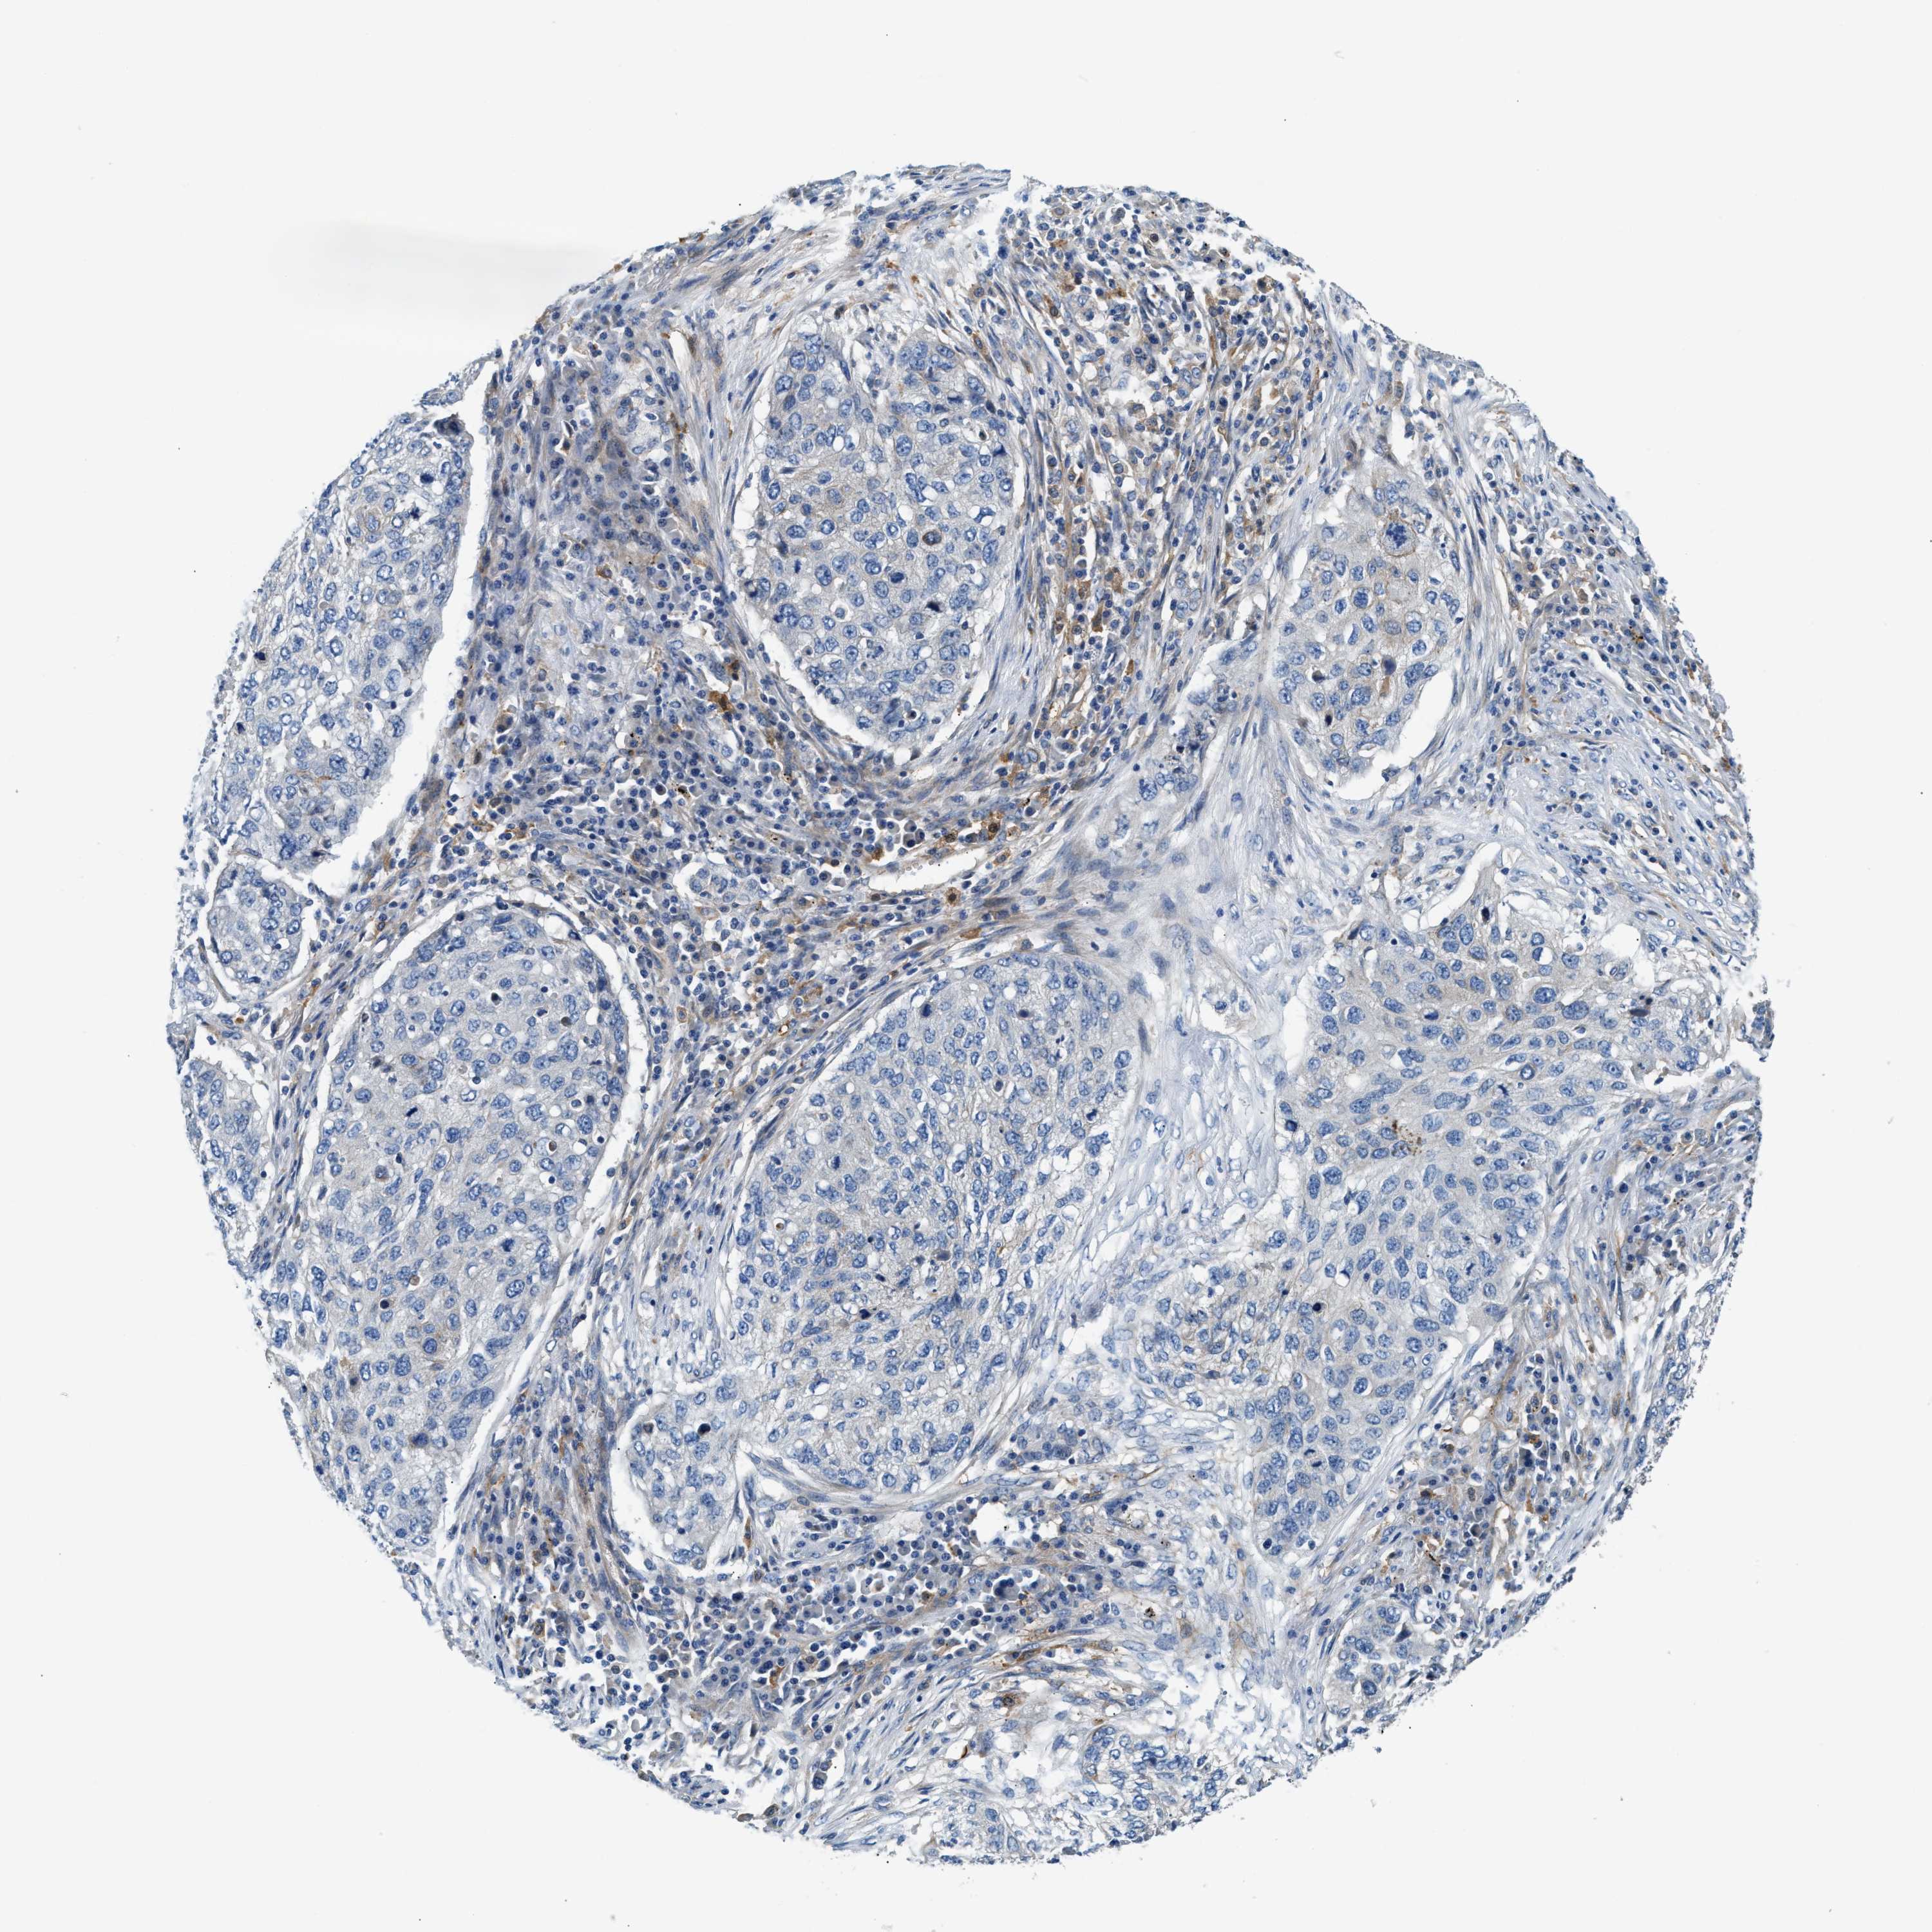

TCGA-77-8148-01A 68 years, male, stage:Stage IIIA, alive, 2023 days 1.9

LUNG SQUAMOUS CELL CARCINOMA (TCGA) - Interactive survival scatter ploti

The Survival Scatter plot shows the clinical status (i.e. dead or alive) for all individuals in the patient cohort, based on the same data that underlies the corresponding Kaplan-Meier plots. Patients that are alive at last time for follow-up are shown in blue and patients who have died during the study are shown in red.

The x-axis shows the expression levels (FPKM) of the investigated gene in the tumor tissue at the time of diagnosis. The y-axis shows the follow-up time after diagnosis (years). Both axes are complimented with kernel density curves demonstrating the data density over the axes. The top density plot shows the expression levels (FPKM) distribution among dead (red) and alive patients (blue). The right density plot shows the data density of the survived years of dead patients with high and low expression levels respectively, stratified using the cutoff indicated by the vertical dashed line through the Survival Scatter plot. This cutoff is automatically defined based on the FPKM cutoff that minimizes the p-score. The cutoff can be changed by dragging the vertical line or by entering a cutoff value in the square labeled "Current cut-off".

Under the Survival Scatter plot the p-score landscape (black curve; left axis) is shown together with dead median separation (red curve; right axis). Dead median separation is the difference in median mRNA expression between patients who have died with high and low expression, respectively. It is calculated as follows: median FPKM expression of dead patients with high expression - median FPKM expression of dead patients with low expression. This is intended to aid the user in visually exploring custom cutoffs and the associated p-scores and dead median separation.

Individual patient data is displayed and can be filtered by clicking on one or more of the category buttons on the top of the page. Categories describing expression level and patient information include: high, low, alive, dead, female, male and tumor stages. The scale of the x-axis can be toggled between linear and log-scale by clicking on the "x log" button. Mouse-over function shows TCGA ID, patient information and mRNA expression (FPKM) for each patient.

& Survival analysisi

Kaplan-Meier plots summarize results from analysis of correlation between mRNA expression level and patient survival. Patients were divided based on level of expression into one of the two groups "low" (under cut off) or "high" (over cut off). X-axis shows time for survival (years) and y-axis shows the probability of survival, where 1.0 corresponds to 100 percent.

NSUN7 is not prognostic in Lung Squamous Cell Carcinoma (TCGA)

TCGA RNA samplesi

RNA-seq data is reported as average FPKM (number Fragments Per Kilobase of exon per Million reads), generated by the The Cancer Genome Atlas (TCGA) .

Normal distribution across the dataset is visualized with box plots, shown as median and 25th and 75th percentiles. Points are displayed as outliers if they are above or below 1.5 times the interquartile range. FPKM values of the individual samples are presented next to the box plot.

Average pTPM 1.6

Number of samples 489